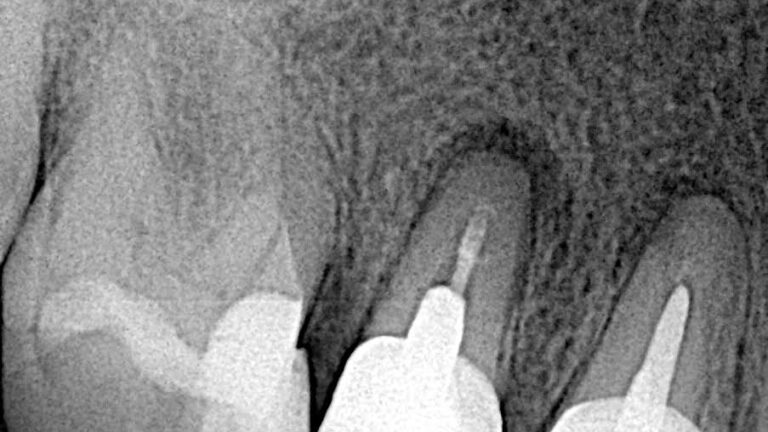

Los casos de retratamiento a menudo se complican y es por eso por lo que el retratamiento requiere…